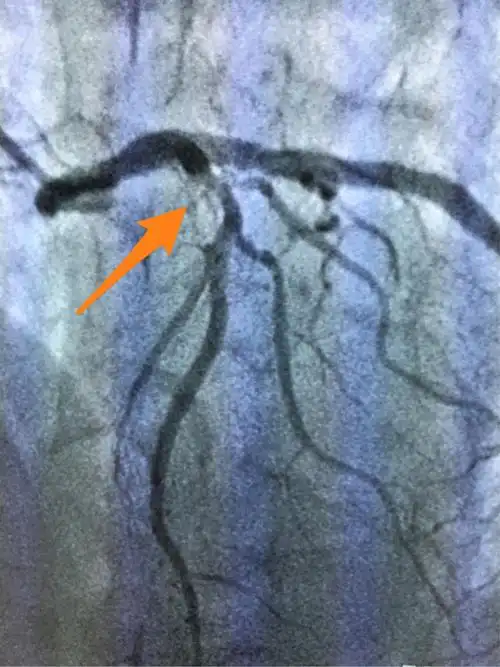

前降支植入一枚支架后影像资料

造影结果显示前降支闭塞

术前:前降支近段弥漫性狭窄最重约90%